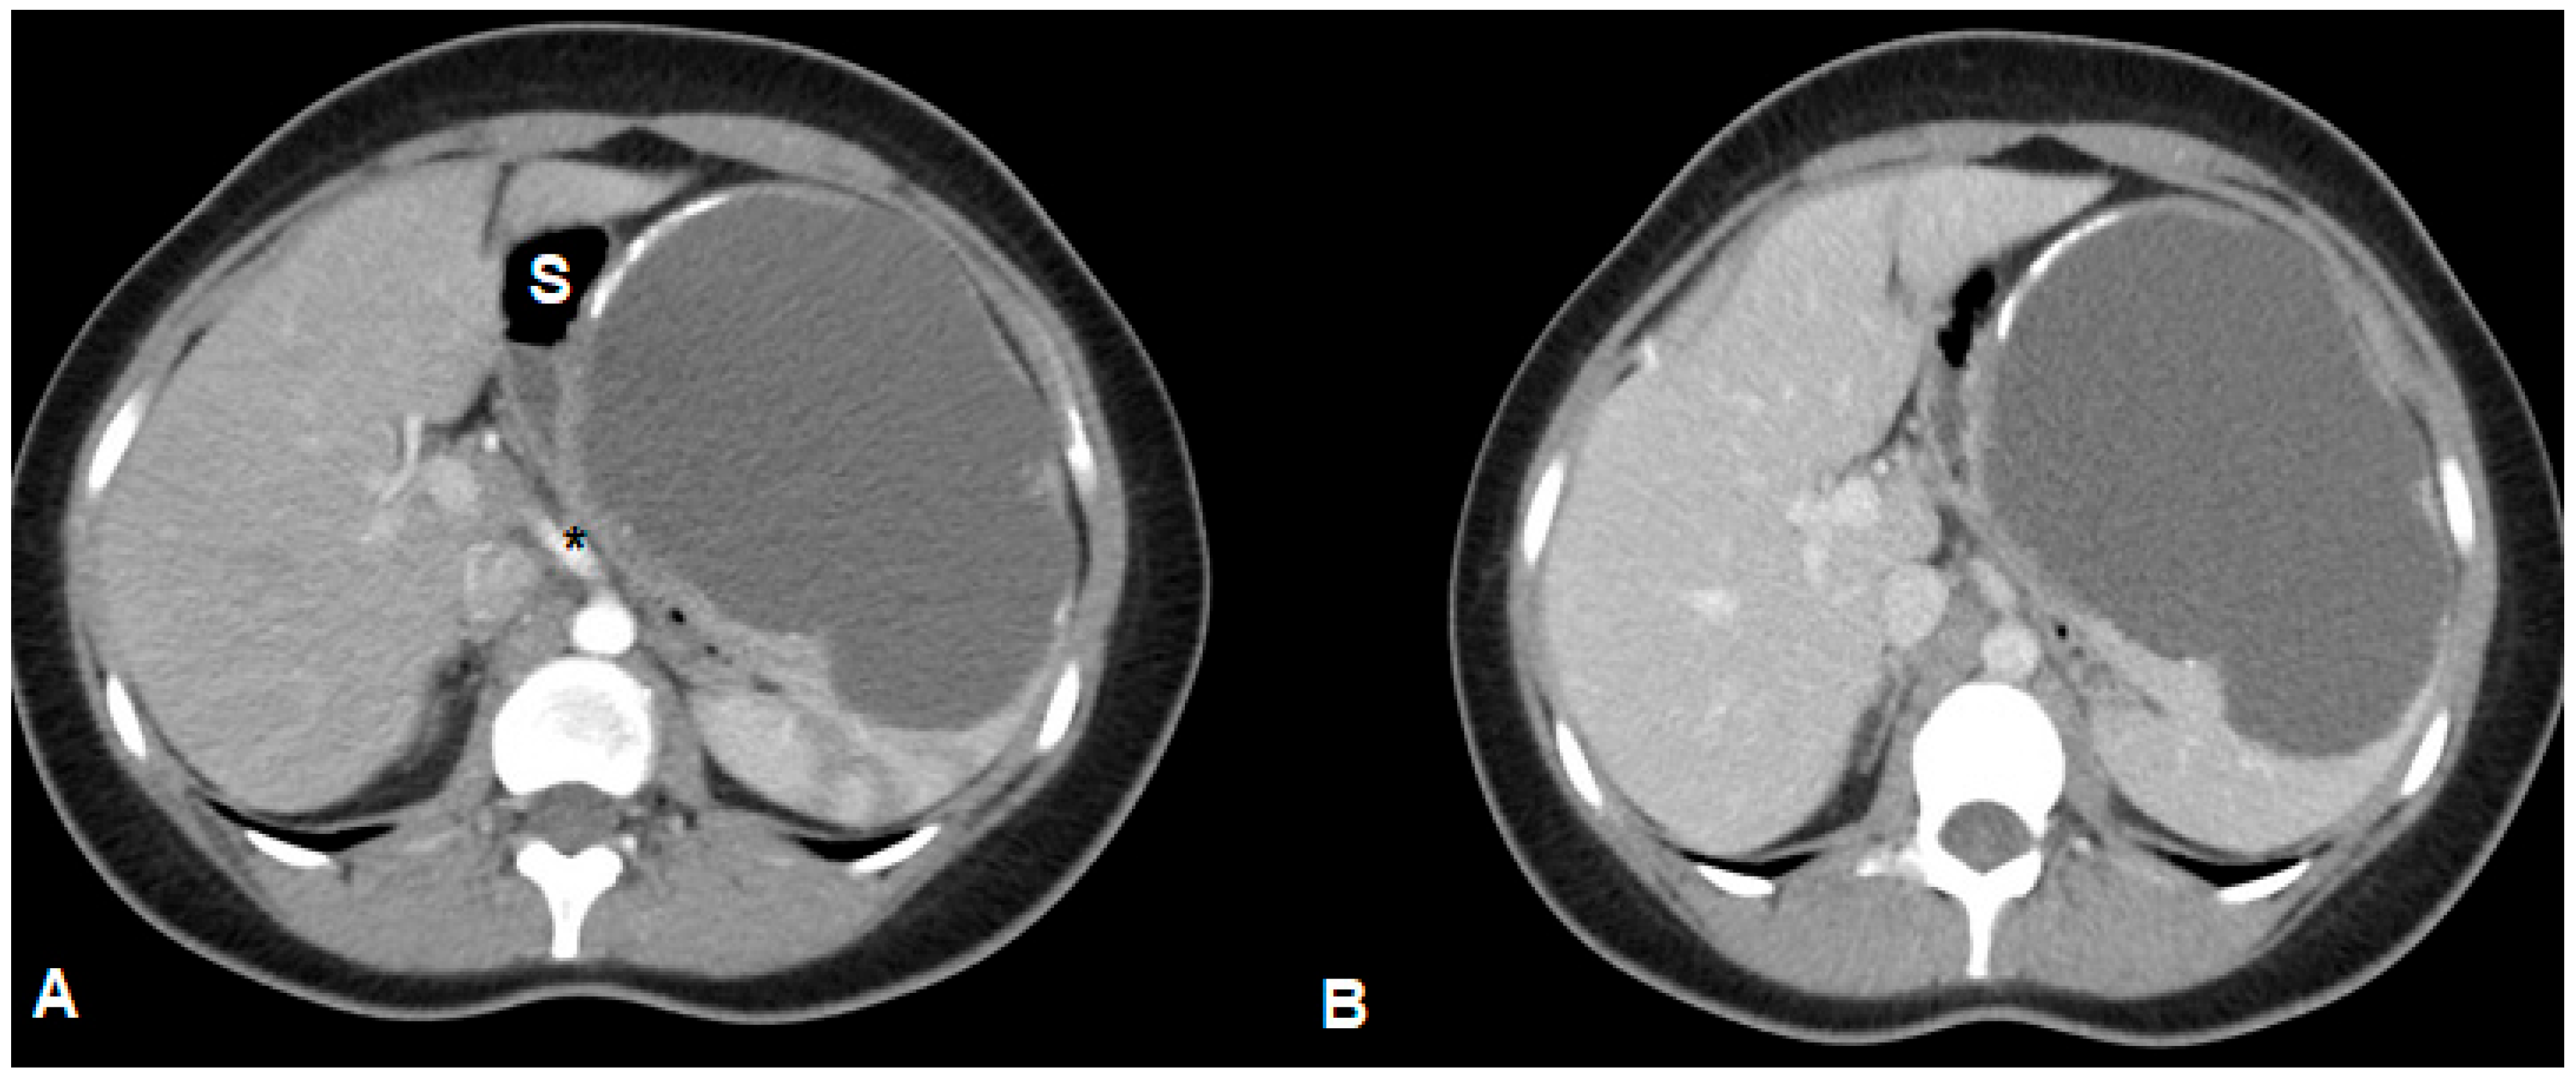

2. Case Presentation